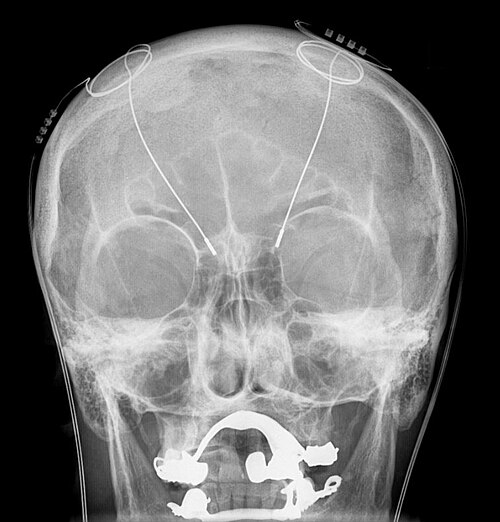

Deep Brain Stimulation: A Guide to Relieve Tremors and Restore Quality of Life Living with involuntary tremors or debilitating movement disorders can profoundly impact daily life, stripping away...

DBS Treatment for Parkinson's, Essential Tremor & Dystonia: A New Horizon for Movement Disorders Living with a movement disorder can present significant challenges, impacting everything from simple...

Deep Brain Stimulation: A Breakthrough for Movement Disorders Living with a debilitating movement disorder can profoundly impact every aspect of life, from simple daily tasks to social interactions...